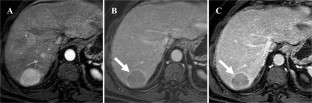

Fig. 2